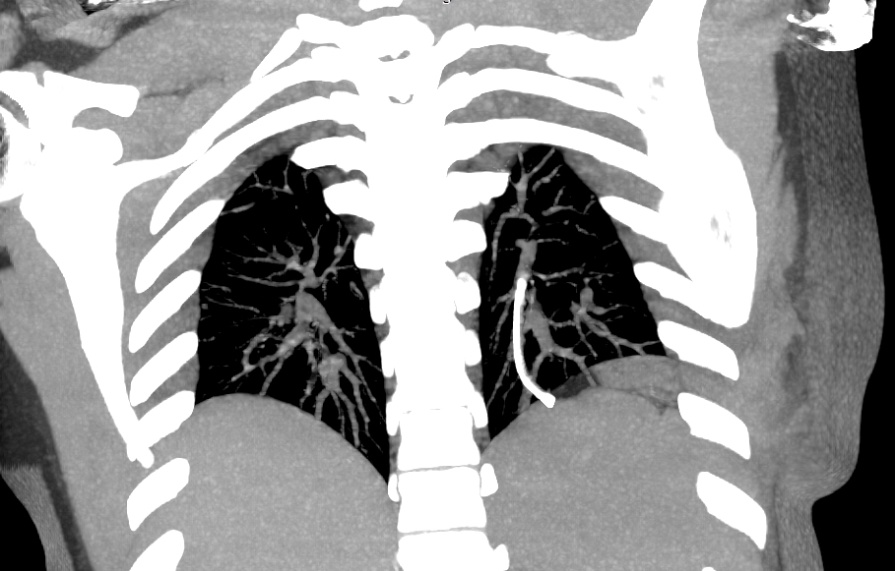

A twenty nine years old lady diagnosed as Carcinoma left breast underwent breast conservation surgery (pT2N2aM0, ER positive PR positive Her 2 neu positive) and presented for adjuvant chemotherapy. She was planned for adjuvant chemotherapy, radiotherapy and hormonal therapy as per standard guidelines. Chemoport reservoir was placed in the chest wall – right infraclavicular fossa and chemoport catheter was placed in the right subclavian vein. Post-procedure chest x ray revealed proper placement of the chemoport. She underwent first cycle of adjuvant chemotherapy with Docetaxel, Carboplatin and Trastuzumab without any complications. When she presented for second cycle (45 days after chemoport insertion), she was asymptomatic. However, there was no backflow of blood from the chemoport reservoir. Chest X ray revealed fragmentation and embolization of chemoport catheter. ECG showed normal sinus rhythm. Non Contrast CT scan chest was done, which revealed that the distal fragment of chemoport catheter had embolized to left pulmonary artery lower lobar branch, having migrated across the right atrium, right ventricle, main pulmonary artery and its left branch (Figure 1). After informed consent, retrieval of distal fragment of chemoport catheter was done in cath lab under local anesthesia under fluoroscopic guidance by Interventional Radiology team. It was retrieved from left pulmonary artery lower lobar branch in a procedure lasting forty minutes. The right femoral vein was punctured, 10 Fr Cordis sheath was introduced into the femoral vein, left pulmonary artery was cannulated using cobra 5 Fr catheter and then it was exchanged with snare over the guide wire. The left posterior inferior branch of pulmonary artery was selectively cannulated using Terumo guide wire and Cobra catheter. The tip of the foreign body was snared using Sequre snare system (4Fr, 10mm) and pulled through the pulmonary artery (Figure 2). The length of the catheter fragment was 4cm (Figure 3-9). The next day, chemoport reservoir and the proximal fragment of chemoport catheter was retrieved by surgery under local anesthesia. Patient tolerated both procedures well and was discharged on the third day.

Figure 1 Magnified Intensity Projection (MIP) image coronal view NCCT Chest showing distal fragment of chemoport catheter in the left pulmonary artery lower lobar branch.